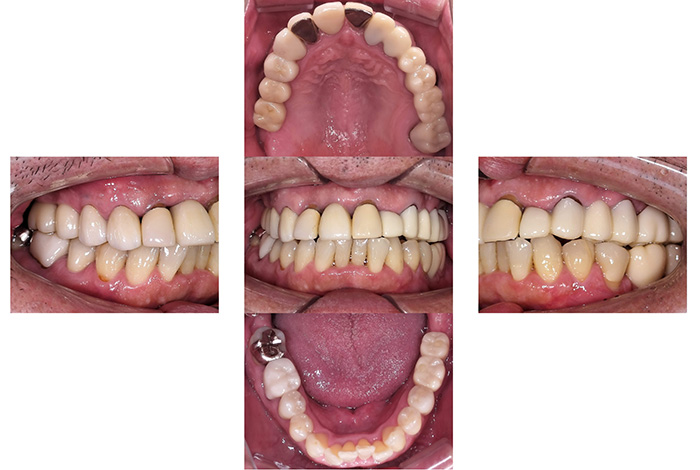

インビザラインによる全体矯正後に補綴治療を行い、咬合と審美性を総合的に改善した症例です。

まずマウスピース型矯正装置(インビザライン)により歯列および咬合関係を整え、その後、必要部位にジルコニア補綴を行いました。

矯正のみ・補綴のみではなく、両治療を組み合わせることで機能性と審美性の両立を目指した包括的治療です。

奥歯の噛み合わせと前歯の歯並びを同時に改善した症例(インビザライン+ジルコニア)

【治療前の状態】

患者様は、奥歯でしっかり噛めないことと、前歯の歯並びの乱れを気にされ来院されました。診査の結果、前歯部の叢生(歯並びの乱れ)と、臼歯部の離開咬合(奥歯がしっかり噛み合っていない状態)が認められました。また、臼歯部には古い金属修復物が装着されており、機能面だけでなく審美面においても改善が必要な状態でした。

【治療後】

前歯の歯並びが整い、見た目の改善が認められました。また、奥歯でしっかり噛める状態となり、咬合機能の回復が得られています。

【治療のポイント】

本症例では、歯並びの改善だけでなく、噛み合わせの回復と審美性の向上を同時に行っています。当院は一般歯科と矯正治療の両方に対応しているため、矯正治療後に別の医療機関で補綴治療を行う必要がなく、一貫した治療計画のもとで治療を完結することが可能です。また、奥歯の噛み合わせを矯正治療のみで改善する場合、治療期間が長くなることがありますが、本症例では補綴治療(アンレー)を併用することで、比較的短期間で咬合の改善を行いました。さらに、古い金属修復物をジルコニアに置き換えることで、見た目の改善と機能性の両立を図っています。